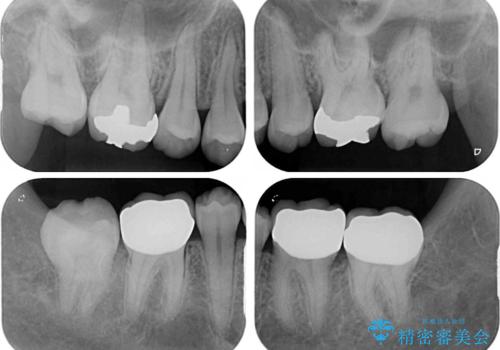

- 奥歯の虫歯と前歯のデコボコや突出感を気にして来院された患者様です。

矯正治療後は、奥歯の虫歯や銀歯を補綴・修復治療することとしました。